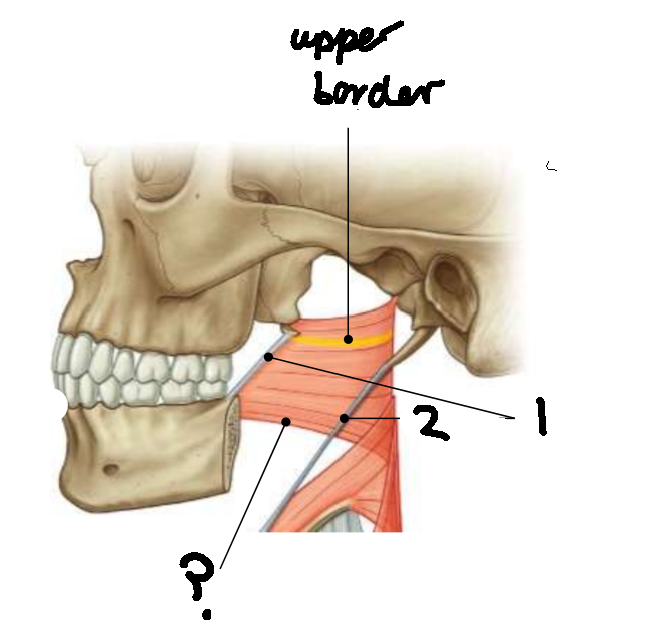

What muscle is this?

superior constrictor

What is the upper border of this muscle?

palatopharyngeal sphincter

What is 1?

pterygomandibular raphe

What is 2?

stylohyoid ligament

What are the attachments of this muscle?

pterygoid hamulus, pterygomandibular raphe, posterior end of mylohyoid line → pharyngeal raphe